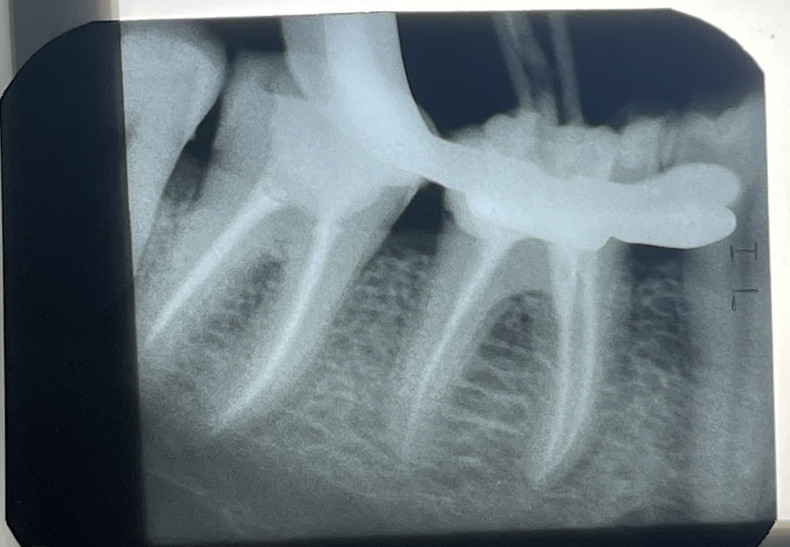

При відсутності вчасного лікування карієсу, інфекція з каріозної порожнини проникає в пульпу зуба викликаючи її запалення,що супроводжується самовільними ,ниючими болями в ділянці ураженого зуба. Така патологія потребує лікування кореневих каналів, що необхідно робити якісно , з обовʼязковою ізоляцією системою кофердам та під рентгенологічним контролем. Вказана вартість лікування 1 кореневого каналу.